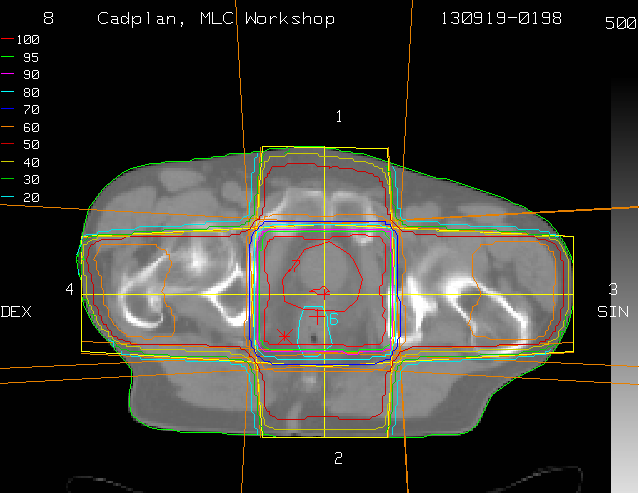

Der fertige Planungsschnitt (transversal): (DRR frontal) (Zurück)